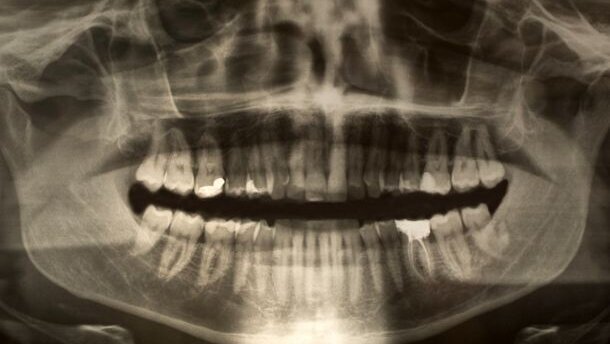

MUMBAI – Een team van Indiase chirurgen heeft bij een zeventienjarige jongen 232 ‘tanden’ verwijderd. De jongen leed aan een goedaardige aandoening waarbij zich in zijn kaak odontomen ontwikkelden. Dit zijn kalkafzettingen in de vorm van een tand.

De jongen had al ruim anderhalf jaar last van zwellingen en pijn aan zijn kaak en gezicht. Zijn vader vreesde dat de jongen een tumor had, en ging daarom naar het ziekenhuis in Mumbai. Daar bleek dat het ging om een goedaardige aandoening, maar wel in extreme mate.

De ingreep om de ‘tanden’ te verwijderen duurde uiteindelijk ruim zeven uur. Sunanda Dhivare-Palwankar, chirurg en hoofdbehandelaar van de jongen, vertelde persbureau AFP dat ze in eerste instantie dachten dat het een simpele ingreep zou zijn. “Maar nadat we het kaakbot hadden blootgelegd, ontdekten we zeer veel parelachtige ‘tanden’ die we moesten verwijderen.” Sommige daarvan waren zo groot en hard, dat ze eerst gefragmenteerd moesten worden voordat ze konden worden verwijderd.

Volgens Dhivare-Palwankar is het aantal verwijderde odontomen uitzonderlijk. “Voor zover wij konden nagaan in de literatuur over deze aandoening, zijn er nooit meer dan 37 odontomen bij één patiënt verwijderd. Deze operatie zou dus weleens een wereldrecord kunnen zijn.”

Bij de operatie is de structuur van het kaakbot behouden gebleven, waardoor het aangezicht van de jongen waarschijnlijk zonder misvormingen zal herstellen.